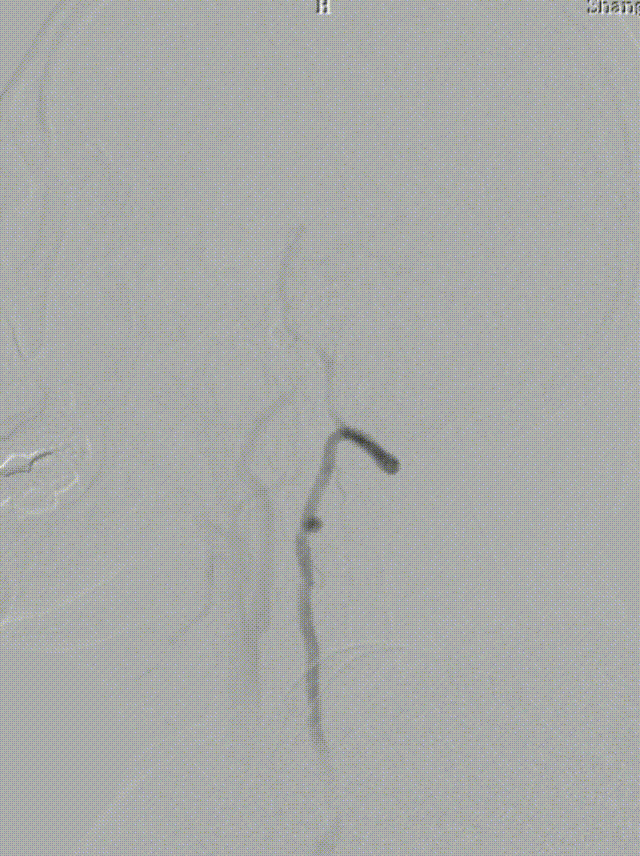

DSA:LSub。

DSA:L-CCA。

0.018*300cm 外周导丝至左肱动脉,0.014*200cm 通桥北斗SS™神经血管导丝超选至左椎V2段远端。

沿0.018*300cm 外周导丝送入6*40 外周球囊送至左侧锁骨下动脉狭窄处,压力泵逐渐加压到6atm。

撤出球囊后见残余狭窄40%。

再次沿0.018*300cm 外周导丝送入6*40 外周球囊达LSub狭窄部位,压力泵逐渐加压到8atm,见残余狭窄20%。

造影见LV闭塞,立即沿0.014*200cm 通桥北斗SS™神经血管导丝置入3mm*16mm 药物球扩支架至LV1。

压力泵逐渐加压球扩支架到8atm, 支架打开良好,造影示残余狭窄0%。

双侧锁骨下动脉造影见椎动脉、基底动脉血流通畅,远端未见栓塞表现。